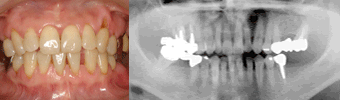

- Case4 / 智歯の移植、部分矯正、インプラント

- 治療期間:2年

治療前

口呼吸が影響して歯肉の炎症が強く出ています。

治療後

歯周治療により歯肉の炎症は改善して綺麗なピンク色になりました。智歯の移植・インプラントを利用することでブリッジ(他の歯を削る)を避けて全体の治療をしました。